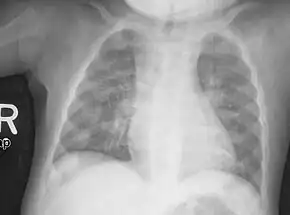

Rachitic rosary on chest radiograph

The prominent knobs of bone at the costochondral joints of rickets patients are known as a rachitic rosary or beading of the ribs. The knobs create the appearance of large beads under the skin of the rib cage, hence the name by analogy with the beads of a Catholic Christian rosary.[1]

Palpation ( Beads formation) , on chest X-ray